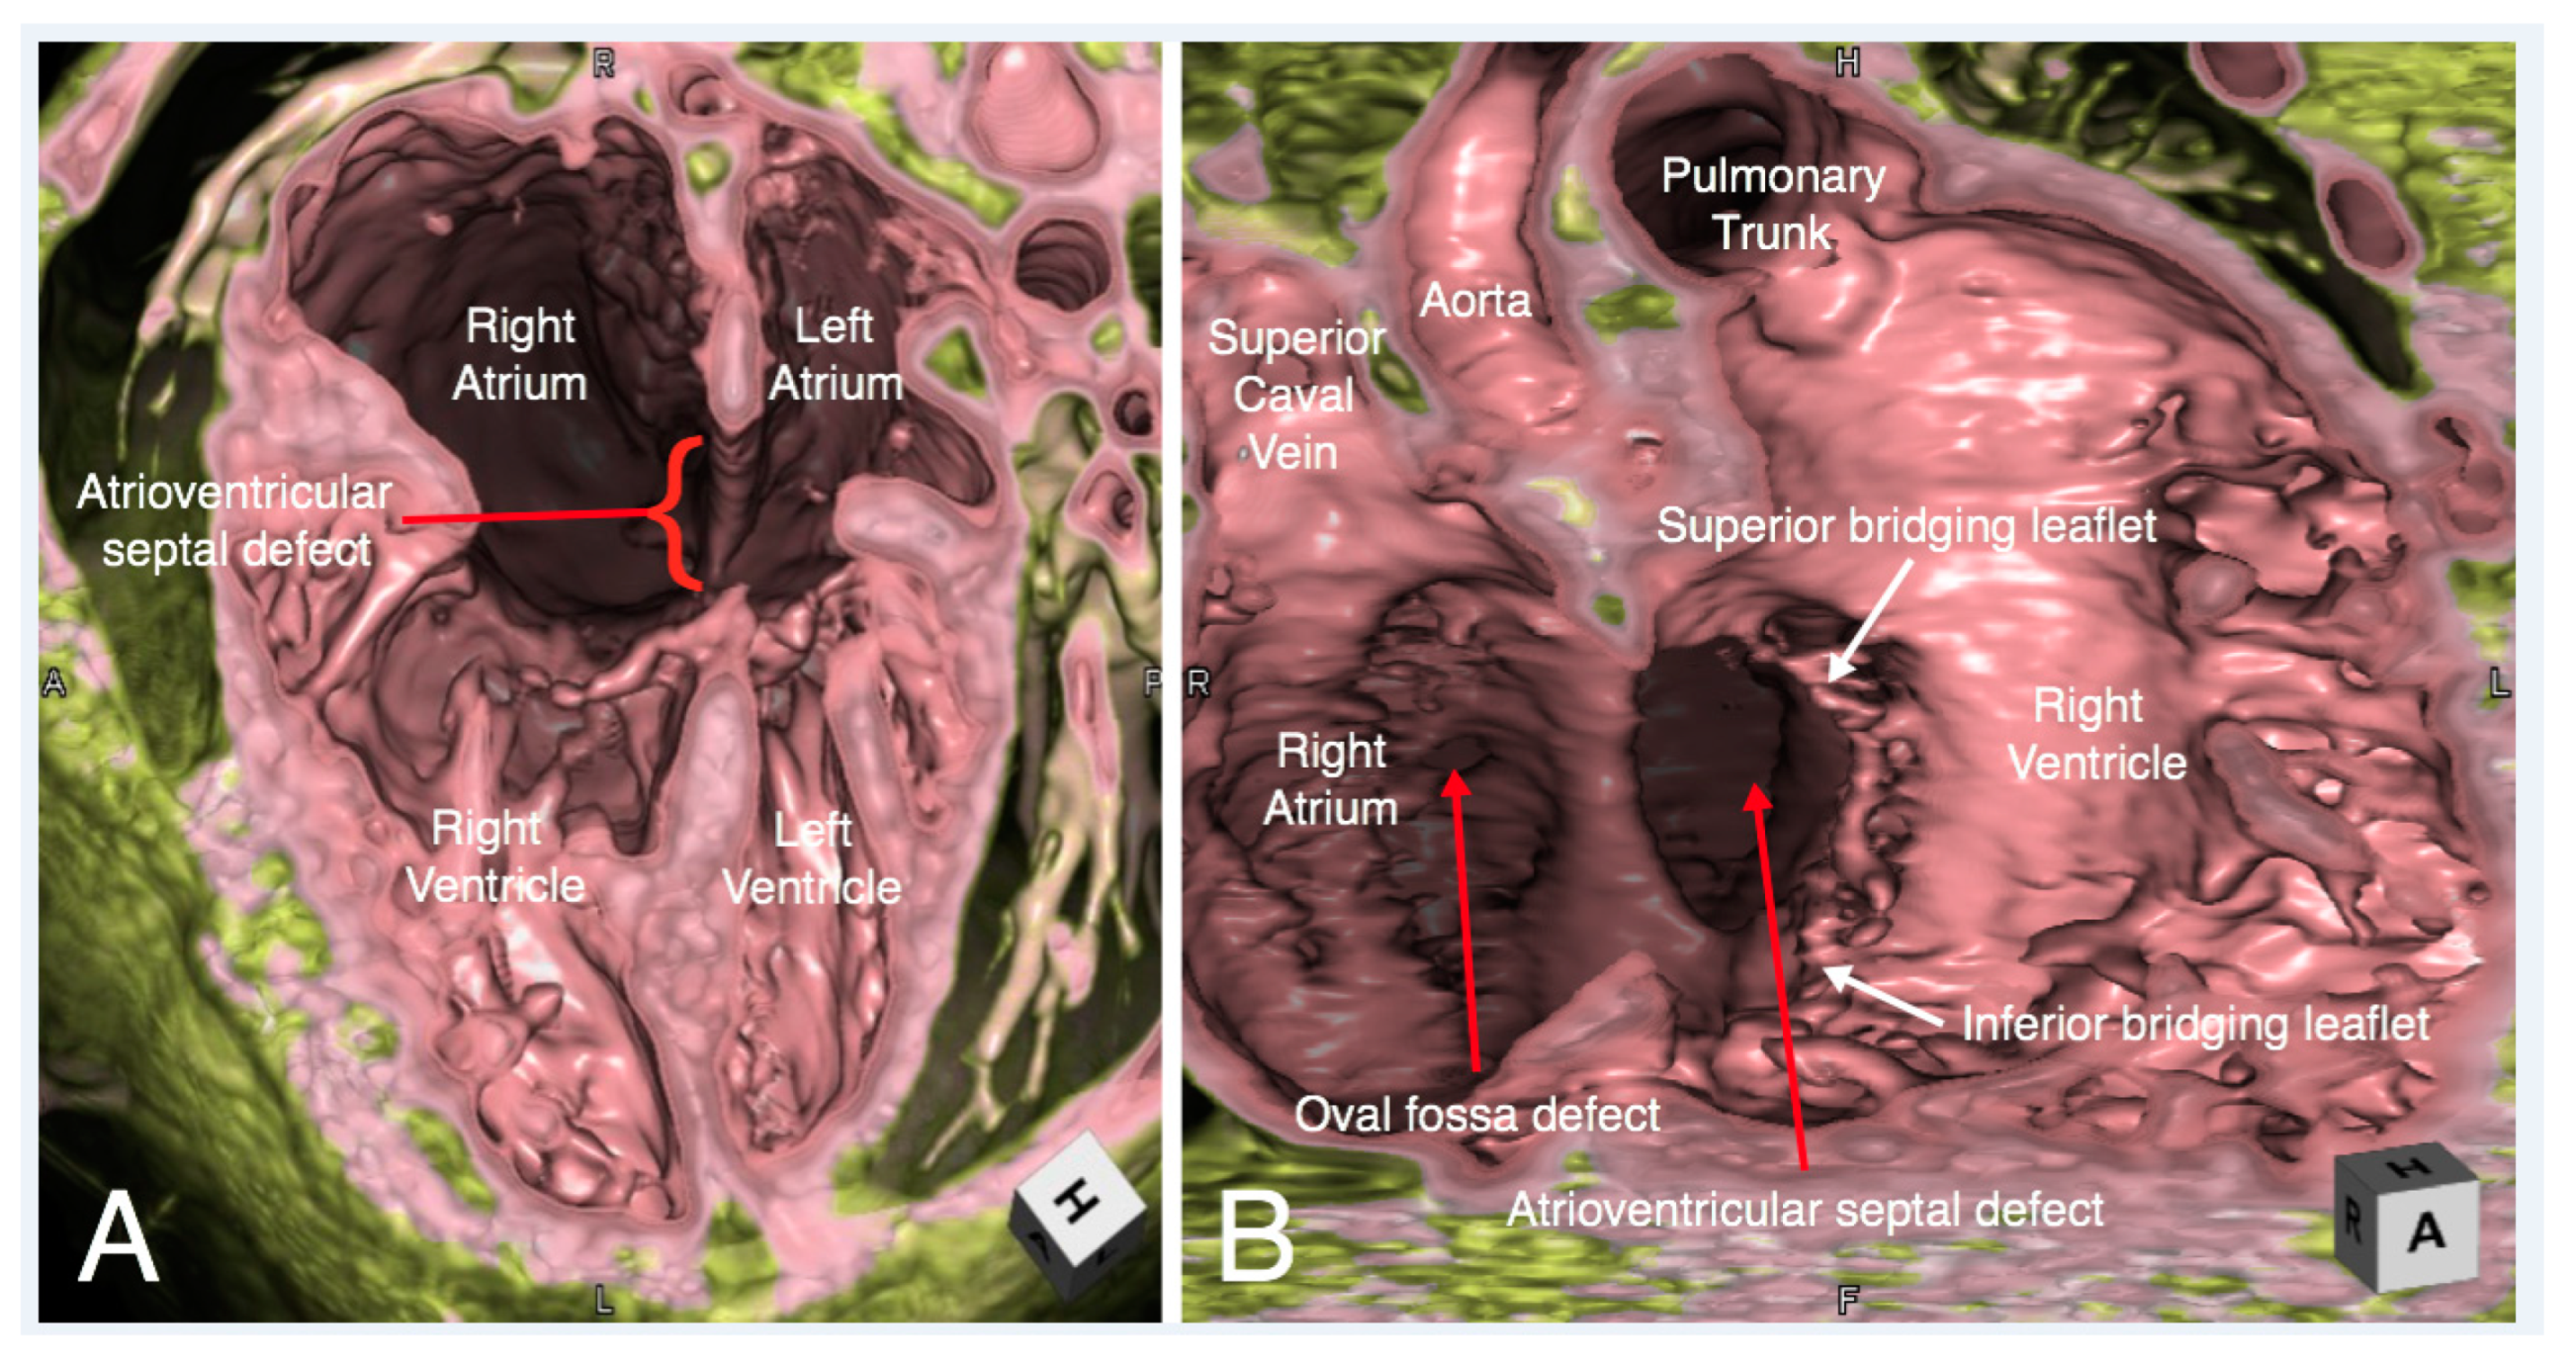

6. Clinical Implication in Congenital Heart Disease with Representative Cases